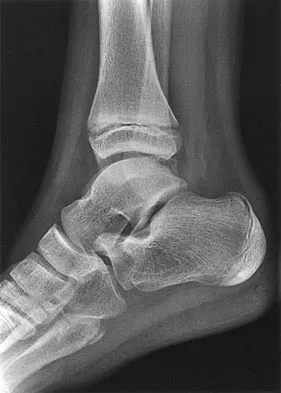

Question 48High Yield

An 11-year-old boy has had a fever and pain and swelling over the lateral aspect of his right ankle for the past 3 days. Examination reveals warmth, swelling, and tenderness over the lateral malleolus, and he has a temperature of 103.2 degrees F (39.5 degrees C). Laboratory studies show a WBC count of 13,200/mm3 with 61% neutrophils, an erythocyte sedimentation rate of 112 mm/h, and a C-reactive protein of 15.7. Radiographs and a T2-weighted MRI scan are shown in Figures 13a through 13c. Aspiration yields 1 mL of purulent fluid. Management should now consist of

Explanation

The initial signs and symptoms of acute hematogenous osteomyelitis vary widely but usually include fever, bone pain, and impaired use of the involved extremity. In lower extremity infections, the child may limp or refuse to walk. Examination often reveals bone tenderness. In more advanced cases, erythema, warmth, and swelling may be present. The WBC and neutrophil counts are not always elevated, but the erythocyte sedimentation rate will be abnormal in more than 90% of patients. When the infection is diagnosed early, before a subperiosteal abscess has formed, antibiotics alone may be adequate to treat the infection. This patient has a more advanced infection, however, with the MRI scan revealing a subperiosteal abscess that was confirmed by aspiration. When an abscess is present, surgical drainage is generally indicated to remove devitalized tissue and to enhance the efficacy of the antibiotics. Further studies, such as bone or indium scans, are not necessary and will delay definitive treatment. Scott RJ, Christofersen MR, Robertson WW Jr, et al: Acute osteomyelitis in children: A review of 116 cases. J Pediatr Orthop 1990;10:649-652.